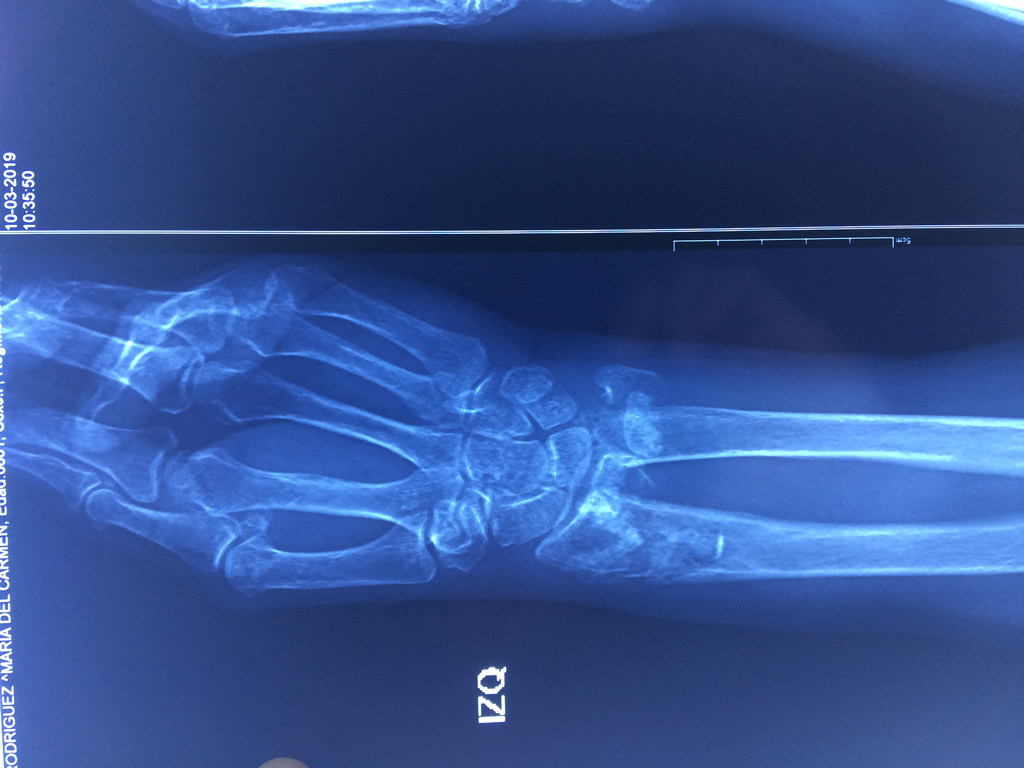

Cirugías de Calcaneo - Cirugías de Muñecas y Manos

Los procedimientos más comunes en cirugía de la mano son aquellos destinados a reparar traumatismos, incluyendo lesiones de tendones, nervios, vasos sanguíneos, y articulaciones; huesos fracturados; y quemaduras, cortes, y otros daños de la piel.